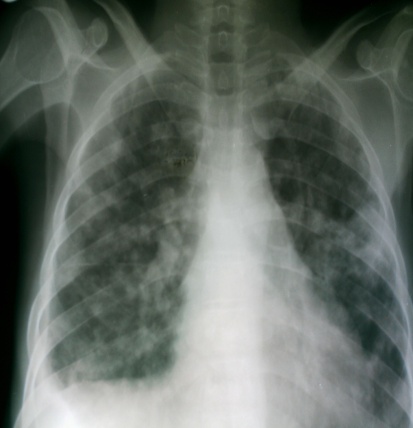

It is important to acknowledge the role of X-ray imaging in the diagnosis of paucibacillary HIV/PTB co-infection and difficult-to-diagnose extrapulmonary TB, since high-tech diagnostic tools such as polymerase chain reaction and nucleic acid line probes are not yet available in our clinic.

Bilateral soft nodular opacities worse in both lower lobes

Right sided pleural effusion with nodular opacities